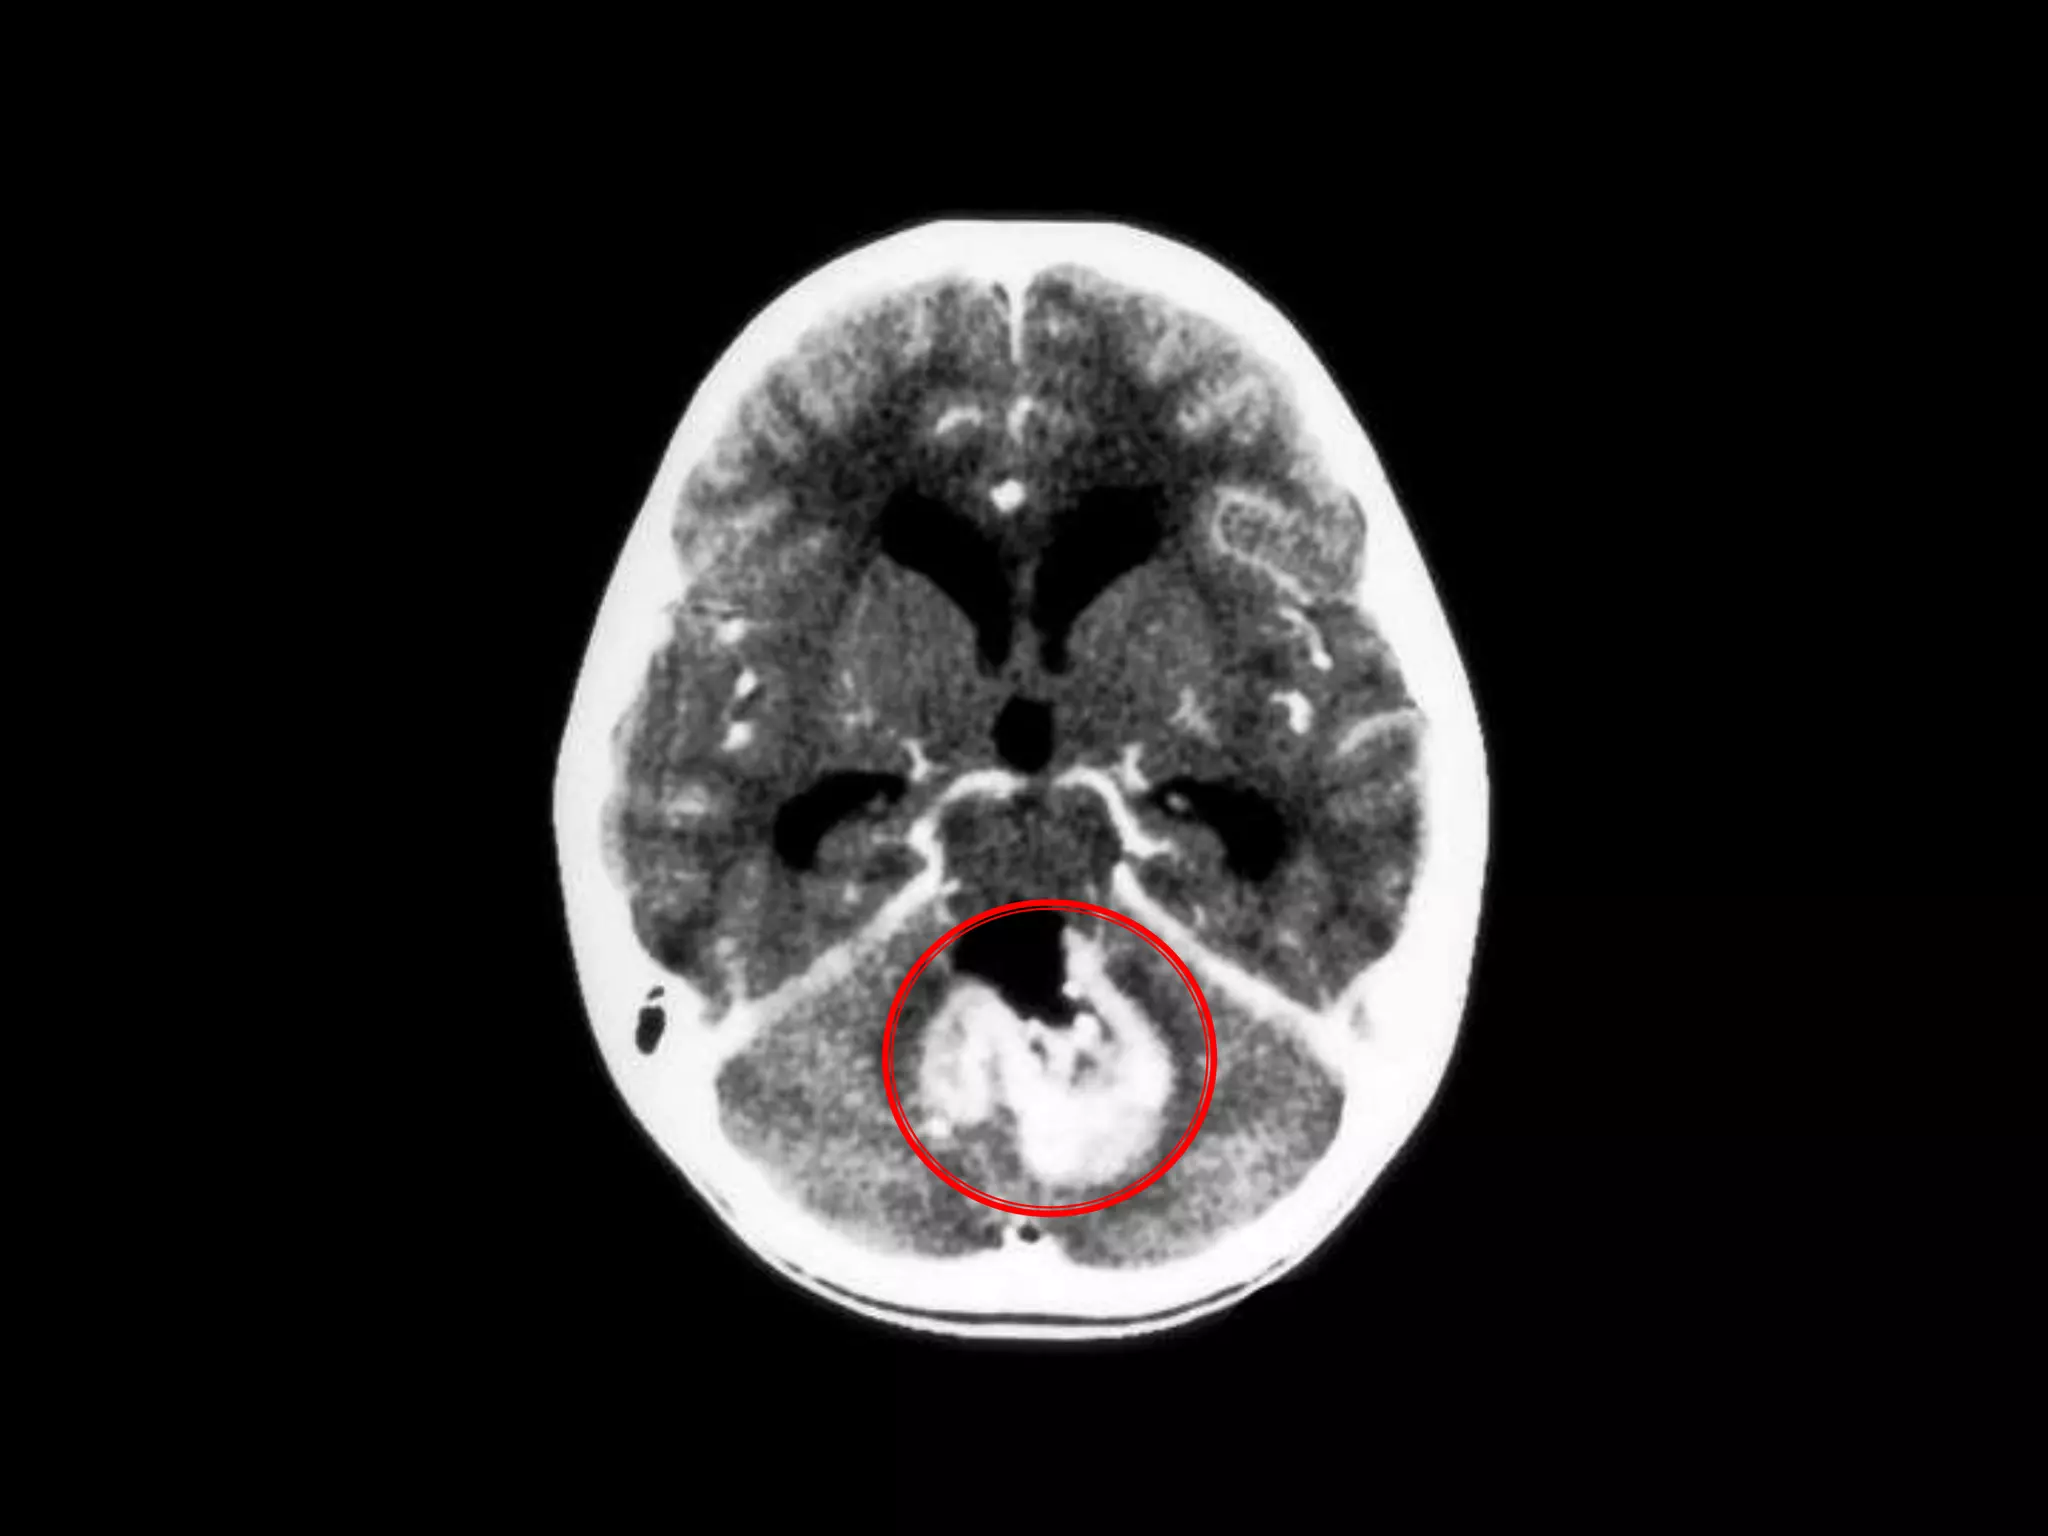

    Red arrow

points to a

large

cerebellar

hemorrhage

Used with permission University of Virginia Health Sciences Center